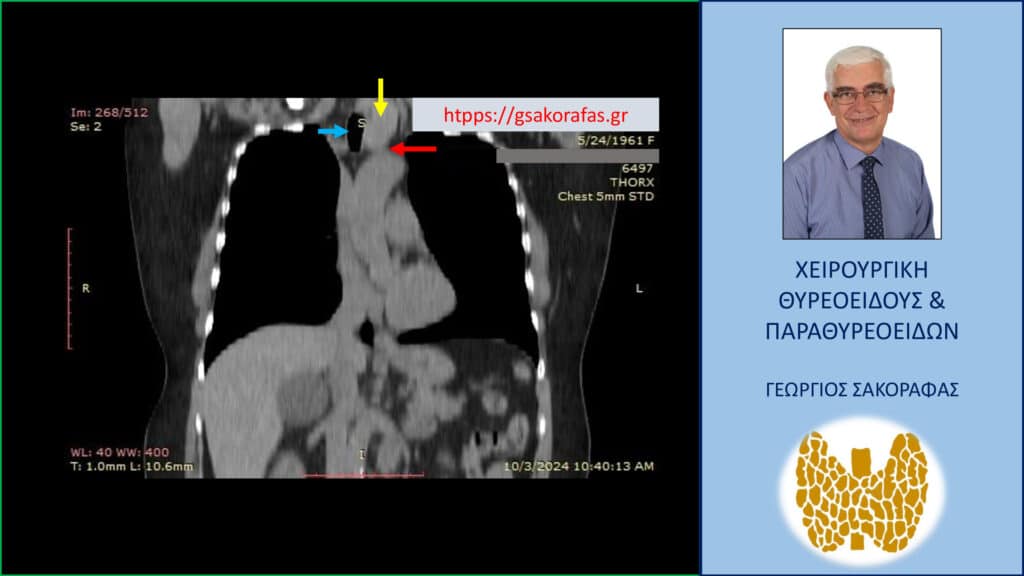

- Αξονική – μαγνητική τομογραφία: μόνο σε πολύ επιλεγμένες περιπτώσεις, όπως π.χ.

– Για την αξιολόγηση της διήθησης παρακειμένων ζωτικών οργάνων (π.χ. τραχείας, οισοφάγου) ή του βαθμού πίεσης αυτών.

– Για την αξιολόγηση του βαθμού κατάδυσης στο ανώτερο μεσοθωράκιο (σε λίαν ευμεγέθεις όζους που καταδύονται οπισθοστερνικά).

Σε επιλεγμένες περιπτώσεις μπορεί να χρειαστεί να συμπεριληφθεί στη κλινική εξέταση αξονική ή μαγνητική τομογραφία (για την αξιολόγηση του βάθους κατάδυσης στο μεσοθωράκιο ενός λίαν ευμεγέθους όζου που προκαλεί πιεστικά φαινόμενα από την τραχεία και για την μέτρηση του εύρους [διαμέτρου] της τραχείας, πράγμα που έχει ιδιαίτερη σημασία για τους αναισθησιολόγους καθώς αναμένονται σε τέτοιες περιπτώσεις δυσκολίες στη διασωλήνωση της τραχείας).